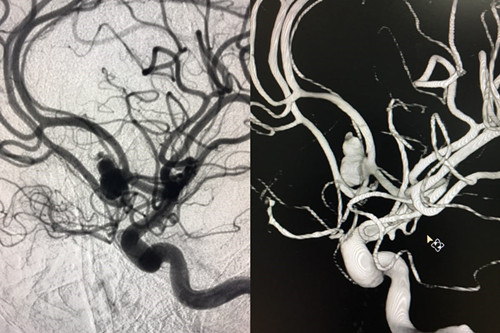

患者赵某,8月28日因“蛛网膜下腔出血”入住我院神经外科。入院时意识呈浅昏迷,且意识障碍进行性加重伴随右侧瞳孔散大,曲友直教授团队根据颅脑CT判定患者为动脉瘤引起的蛛网膜下腔出血。由于动脉瘤在人体内像个定时炸弹,随时会再次破裂,危险性非常大。能否及时为患者实施动脉瘤手术,避免动脉瘤继续破裂,从源头遏制患者病情继续恶化的可能性,直接关系到患者的预后。曲教授团队制定了详细的诊疗计划,在最短时间内为患者行侧脑室外引流术,并及时为患者实施了全脑血管造影,结果证实了术前判断,是大脑前交通动脉瘤,分上下两叶、宽颈。考虑到患者脑肿胀明显,基础状态差,急诊行开颅夹闭手术风险极高,曲友直教授团队反复评估、综合考虑后为患者实施了双导管技术宽颈动脉栓塞术。实施双导管技术避免支架辅助对前交通宽颈动脉瘤进行栓塞,术后患者无须长期口服抗血小板及抗凝药物、为患者术后赢得了进一步康复的机会、减少了长期服药的经济负担。手术过程十分顺利,术后患者病情稳定,正在进一步恢复治疗中。

术前造影